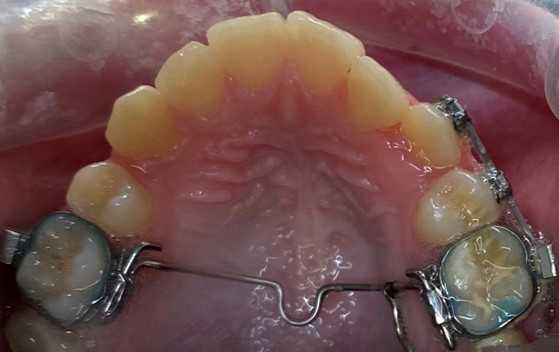

Sidder på tandbånd og ligger langs ganen, for at holde eller ændre på 6-års tænderne i overkæben. Desuden kan den holde eller øge tandbuens bredde.

Det vil være nødvendigt at isætte separationselastikker ved 6-års tænderne.

Placeres mellem 6-års tænderne hvis der skal sættes et bånd rundt om 6-års tænderne.